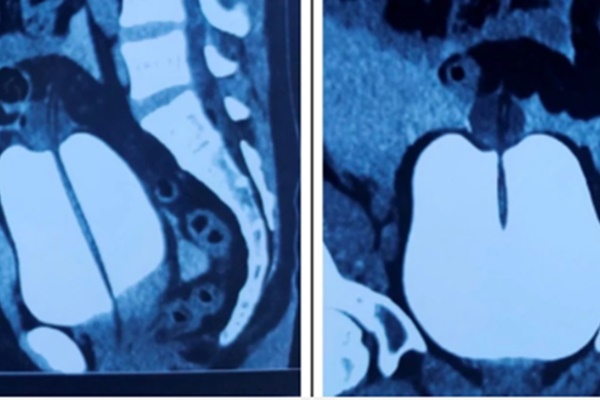

Các bác sĩ kết luận bệnh nhân bị vỡ bàng quang, chấn thương bụng kín nên khẩn trương chỉ định phẫu thuật khâu lỗ thủng bàng quang qua nội soi ổ bụng để ngăn chặn nguy cơ viêm phúc mạc diễn tiến nặng dẫn tới nhiễm trùng máu, sốc nhiễm trùng gây nguy hiểm tính mạng người bệnh.

Bác sĩ chuyên khoa Nguyễn Hoàng Phương, Trưởng Khoa Ngoại thận - Tiết niệu phụ trách chính ca phẫu thuật. Sau 2 giờ đã lấy sạch máu cục, máu loãng, lau rửa ổ bụng, cắt lọc mô, khâu lại vùng bàng quang bị vỡ, đặt dẫn lưu cho bệnh nhân.